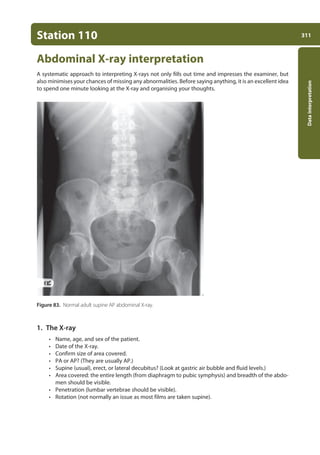

110. Abdominal X-ray interpretation 311